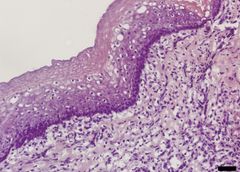

Tissue engineering has been used to construct natural oesophagi, which in combination with bone marrow stem cells have been safely and effectively transplanted in rats. The study, published in Nature Communications, shows that the transplanted organs remain patent and display regeneration of nerves, muscles, epithelial cells and blood vessels.

In this new study, the researchers created the bioengineered organs by using oesophagi from rats and removing all the cells. With the cells gone, a scaffold remains in which the structure as well as mechanical and chemical properties of the organ are preserved. The produced scaffolds were then reseeded with cells from the bone marrow. The adhering cells have low immunogenicity which minimizes the risk of immune reaction and graft rejection and also eliminates the need for immunosuppressive drugs. The cells adhered to the biological scaffold and started to show organ-specific characteristics within three weeks.

The cultured tissues were used to replace segments of the oesophagus in rats. All rats survived and after two weeks the researchers found indications of the major components in the regenerated graft: epithelium, muscle cells, blood vessels and nerves.